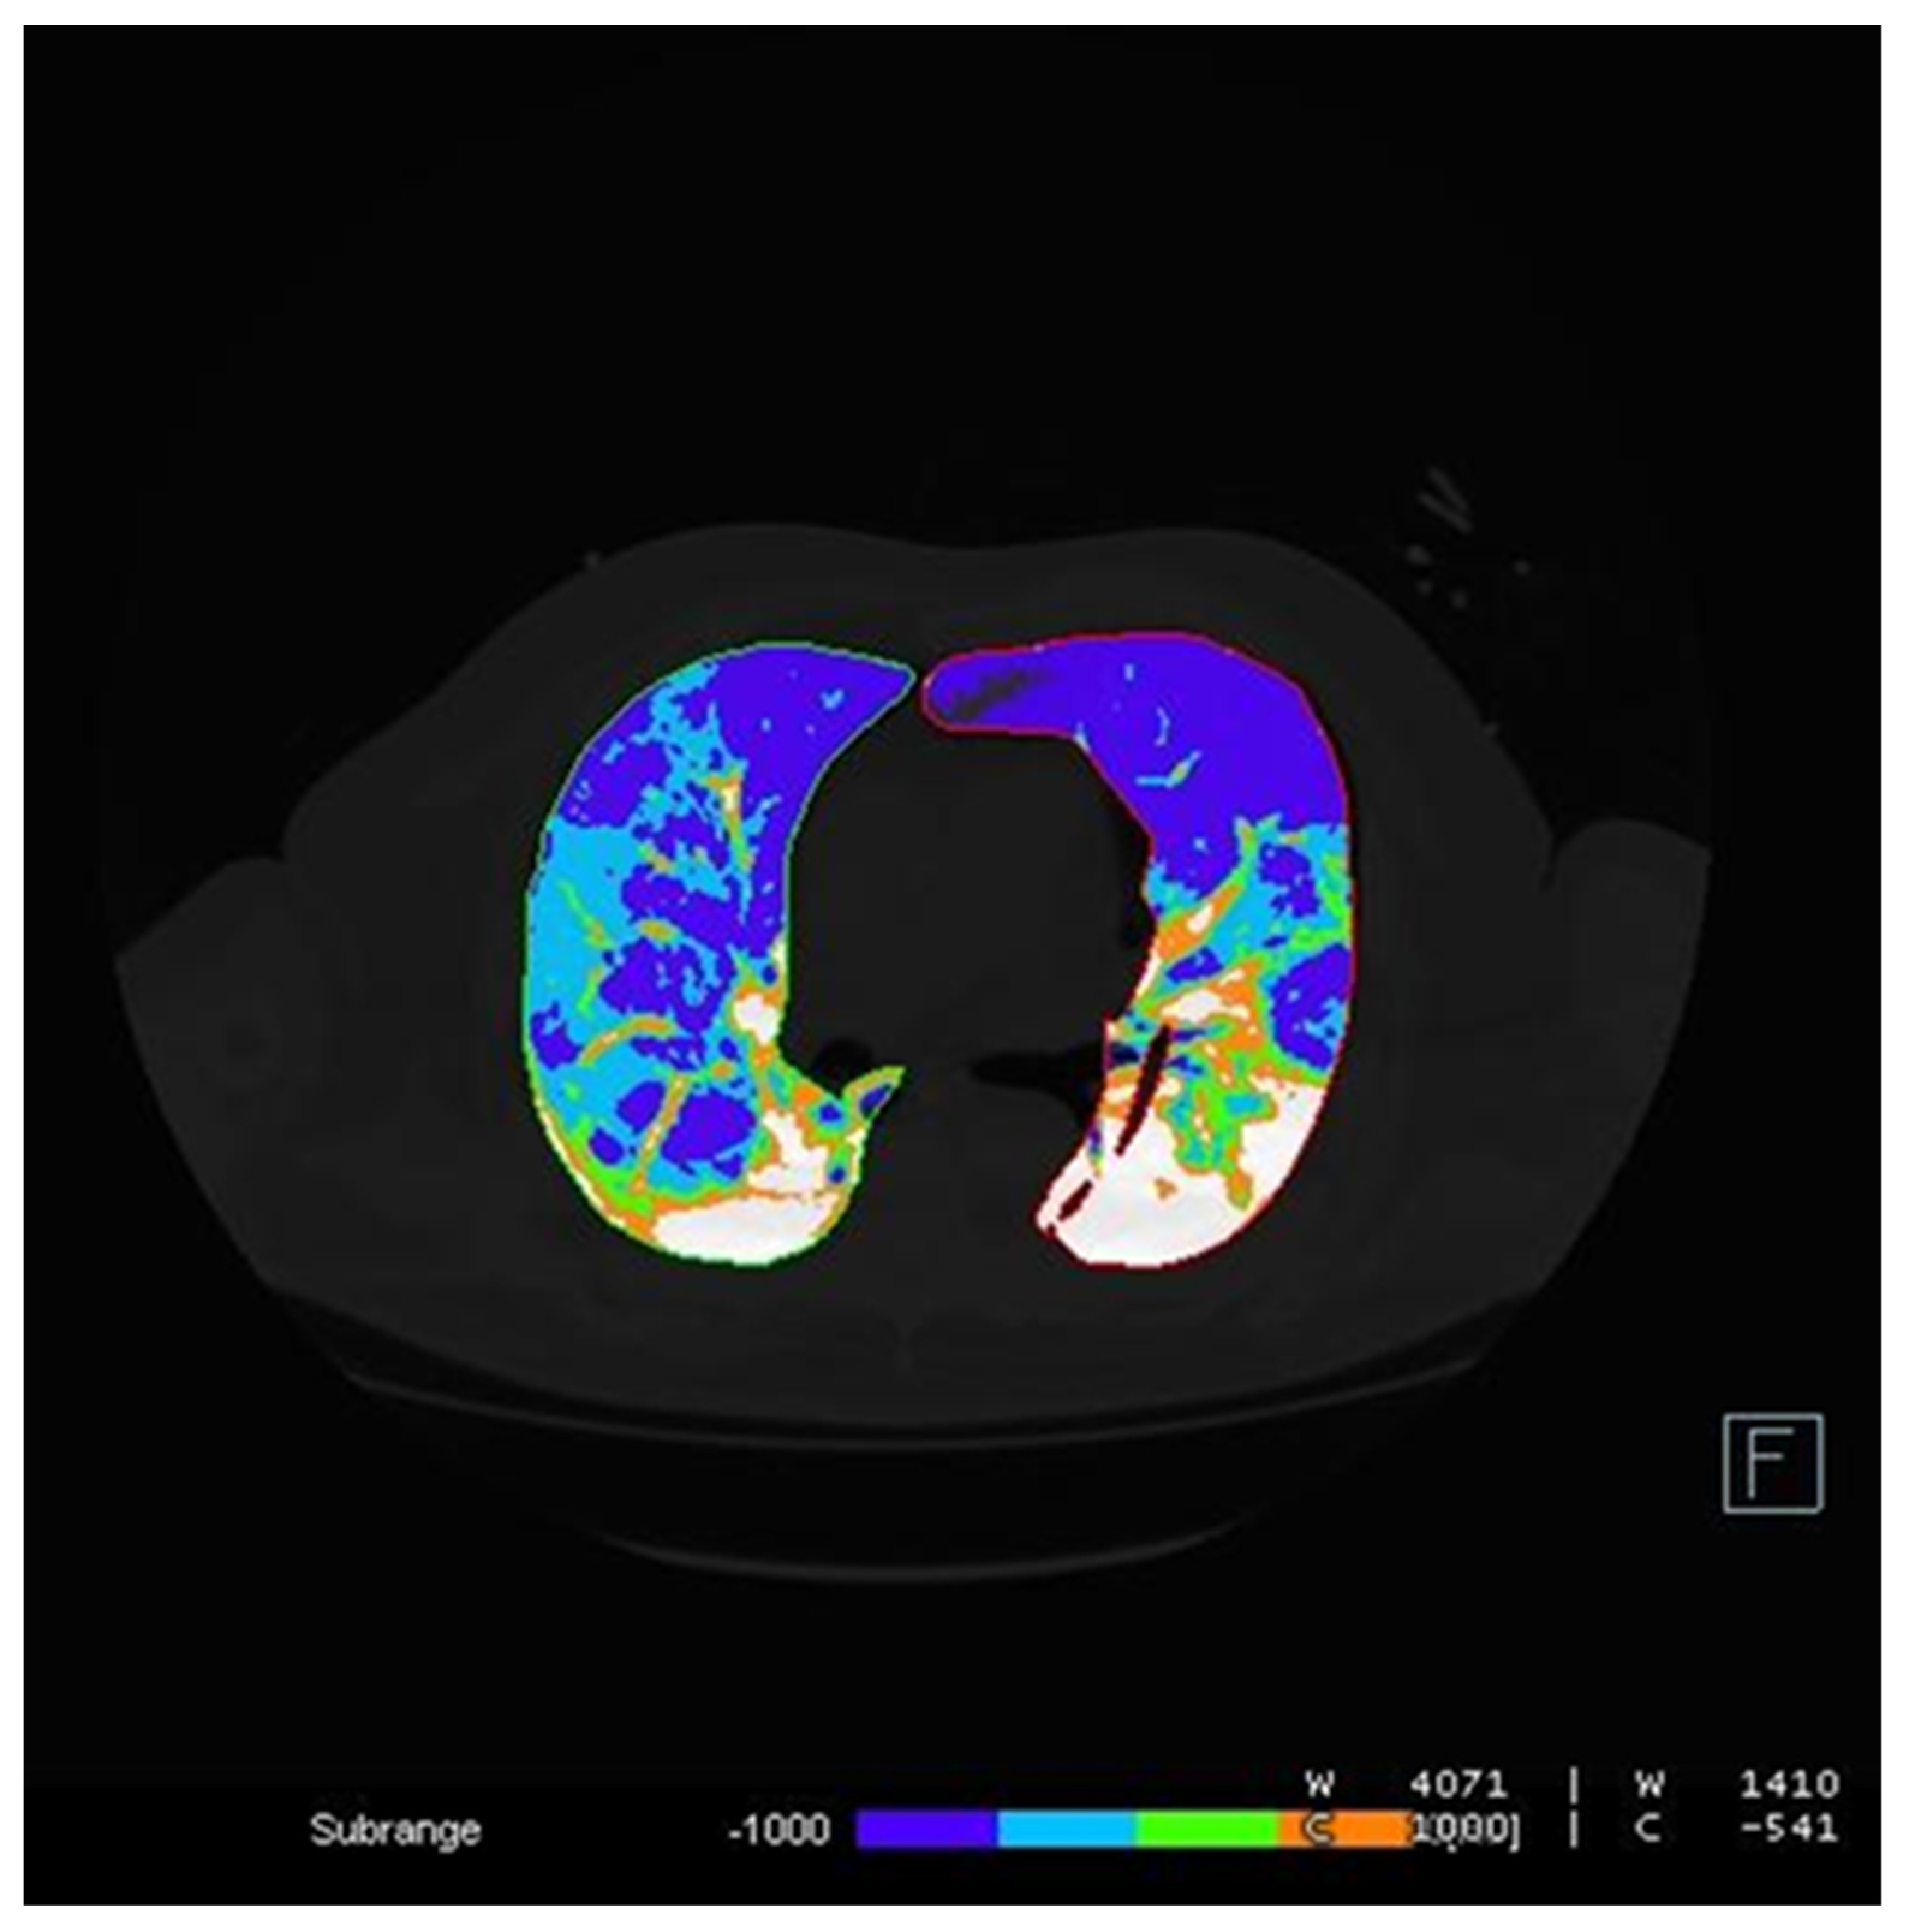

2.3. Image Analysis

| 3DSlicer | 27 | 35 | 46 |

| Canon | 22 | 32 | 43 |

| Siemens | 24 | 32 | 42 |

| ICC = 0.92 | |||